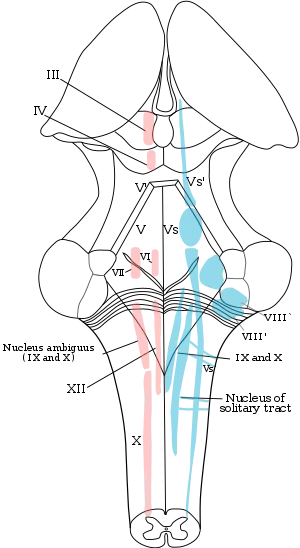

The cranial nerve nuclei schematically represented; dorsal view. Motor nuclei in red; sensory in blue. (The olfactory and optic centers are not represented.) | |

A cranial nerve nucleus is a collection of neurons (gray matter) in the brain stem that is associated with one or more of the cranial nerves. Axons carrying information to and from the cranial nerves form a synapse first at these nuclei. Lesions occurring at these nuclei can lead to effects resembling those seen by the severing of nerve(s) they are associated with. All the nuclei except that of the trochlear nerve (CN IV) supply nerves of the same side of the body.

Motor and sensory

In general, motor nuclei are closer to the front (ventral), and sensory nuclei and neurons are closer to the back (dorsal). This arrangement mirrors the arrangement of tracts in the spinal cord.

- Close to the midline are the motor efferent nuclei, such as the oculomotor nucleus, which control skeletal muscle. Just lateral to this are the autonomic (or visceral) efferent nuclei.

- There is a separation, called the sulcus limitans, and lateral to this are the sensory nuclei. Near the sulcus limitans are the visceral afferent nuclei, namely the solitary tract nucleus.

- More lateral, but also less posterior, are the general somatic afferent nuclei. This is the trigeminal nucleus. Back at the dorsal surface of the brainstem, and more lateral are the special somatic afferents, this handles sensation such as balance.

- Another area, not on the dorsum of the brainstem, is where the special visceral efferents nuclei reside. These formed from the pharyngeal arches, in the embryo. This area is a bit below the autonomic motor nuclei, and includes the nucleus ambiguus, facial nerve nucleus, as well as the motor part of the trigeminal nerve nucleus.